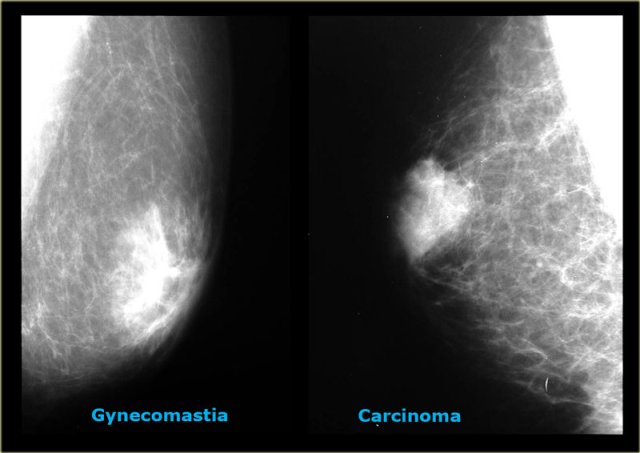

On the left two more cases.

On the far left there is diffuse gynecomastia.

On the right a huge cancer which is encapsulated.

The last cases on the left look very similar to each other.

Based on the mammogram these two can not be differentiated.

In those rare instances a biopsy is needed.